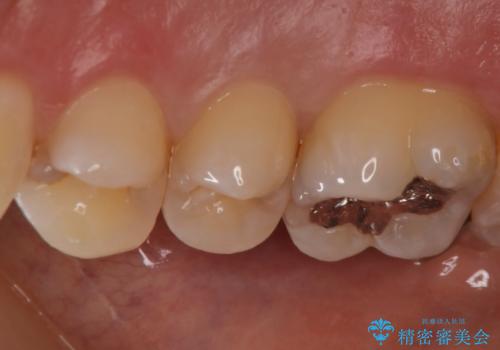

- 歯によく繊維質なものがはさまることが気になり来院されました。レントゲン等から隣接カリエス(歯間にできるう蝕)があることが分かり、清掃性が高く、審美的なセラミックインレーで治療を行いました。